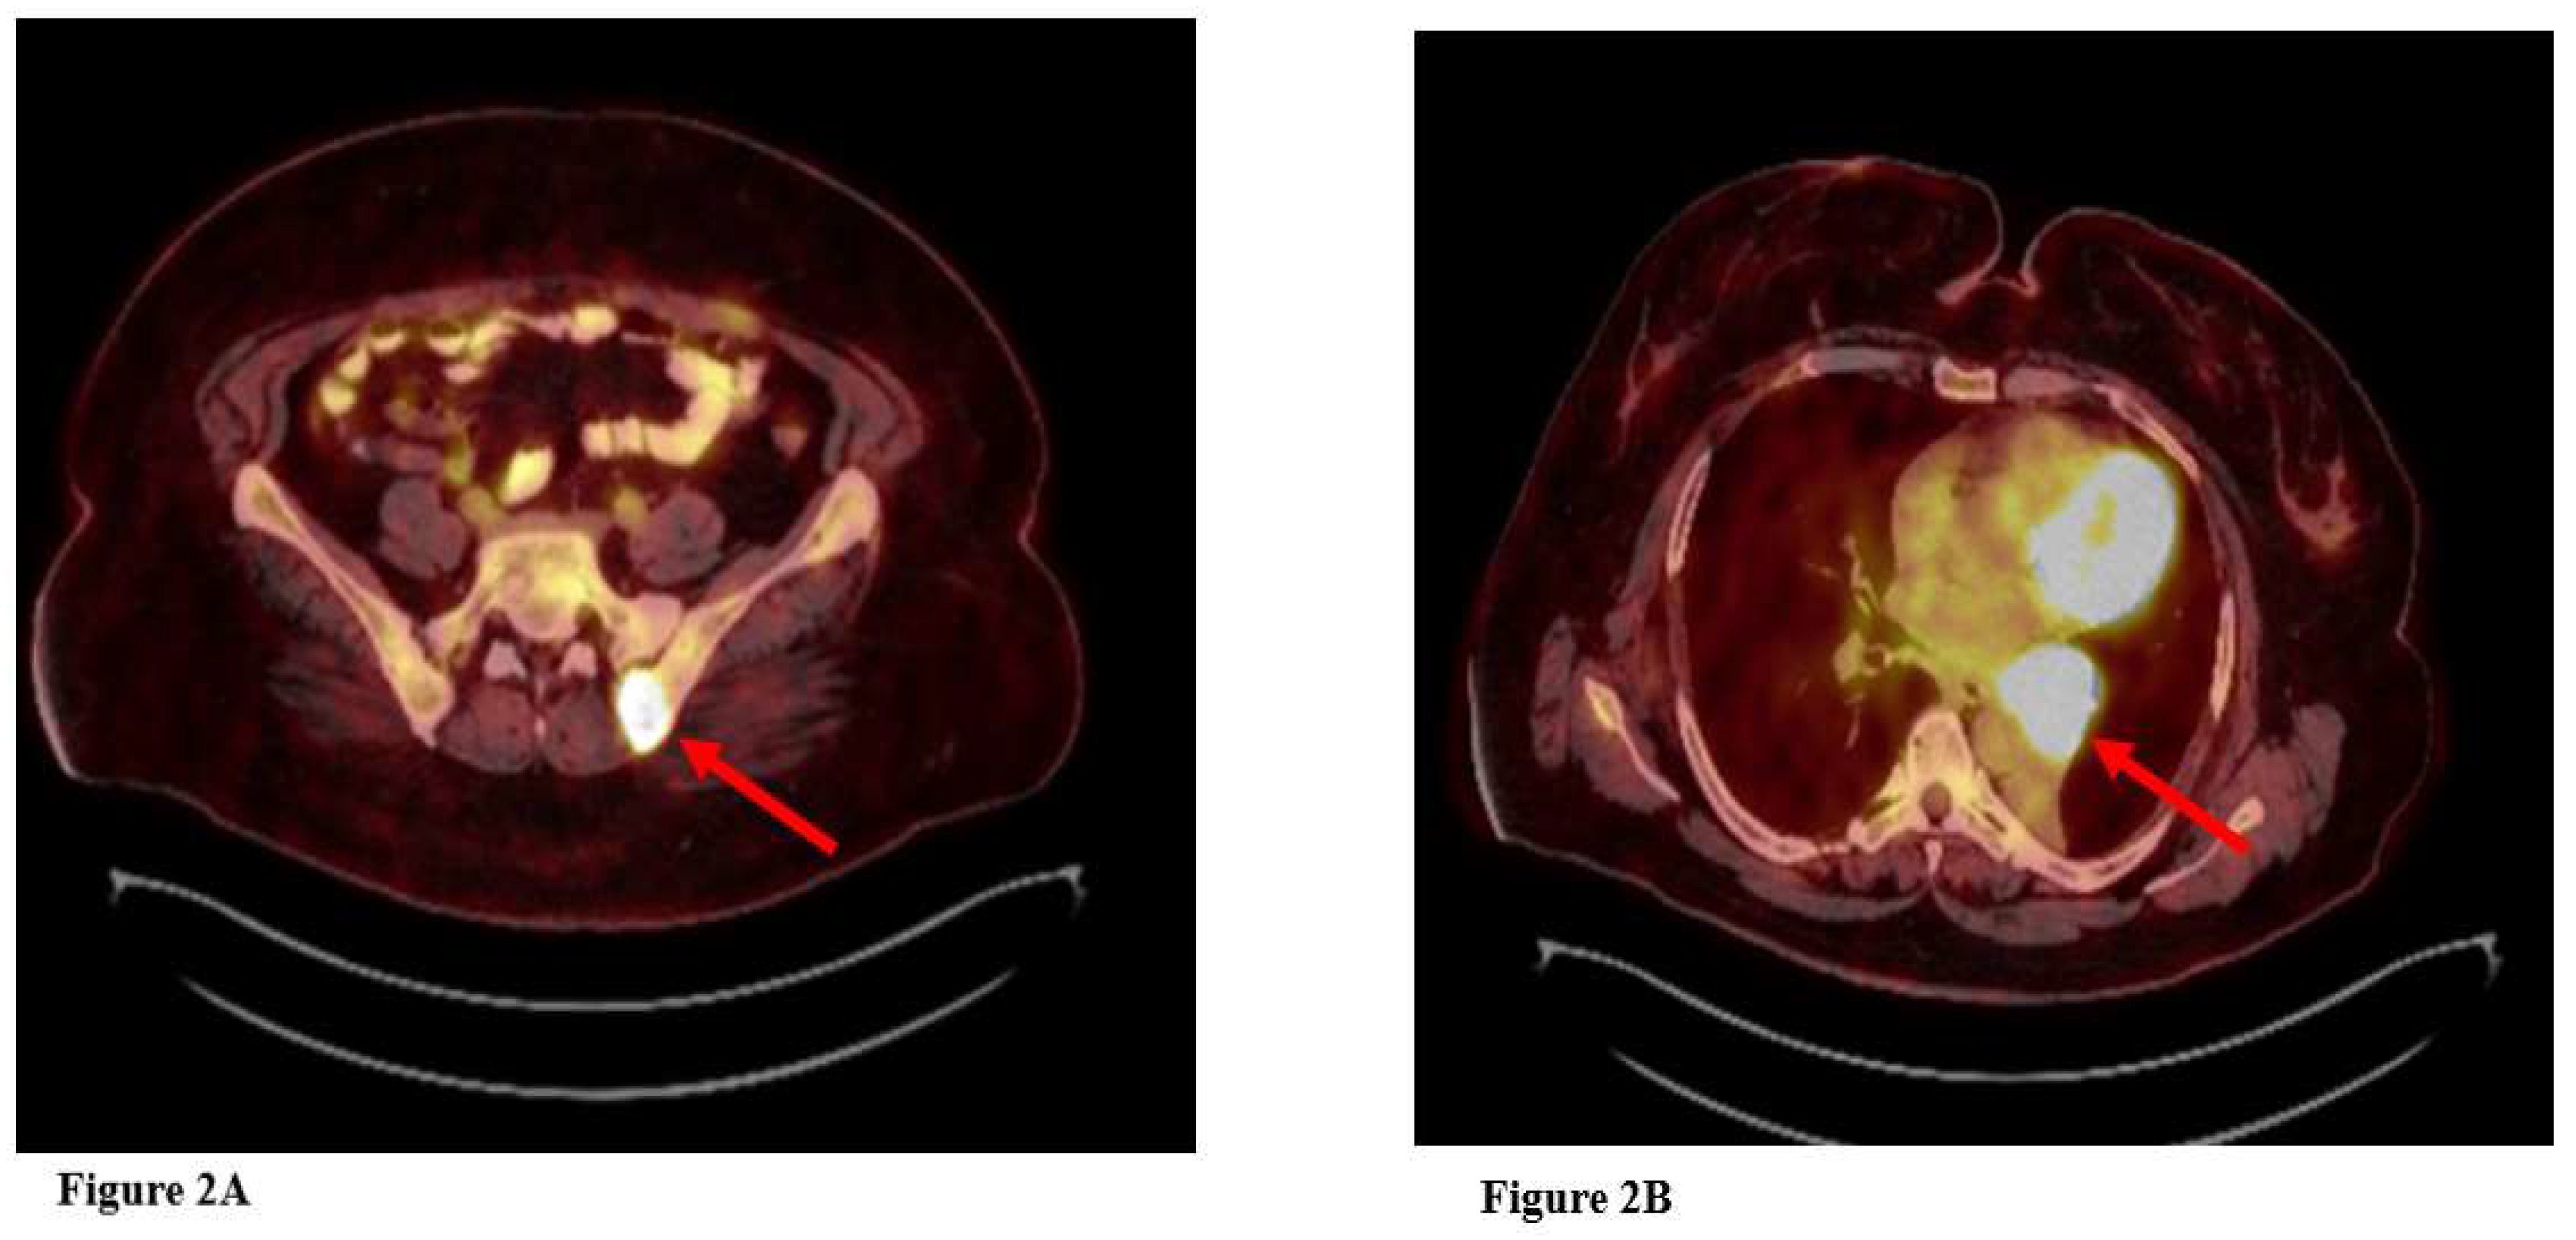

In October 2024, the patient was initiated on crizotinib 2×250 mg tablets, based on the results of the NGS. Within two weeks of treatment, the patient exhibited significant symptomatic relief and substantial tumor regression. No drug-related adverse events were observed. At the three-month follow-up, thoracic CT imaging demonstrated a marked reduction in tumor size compared to three months earlier, accompanied by a completely asymptomatic clinical response. The patient's thoracic CT images before and after treatment are presented in Figure 1, and the PET-CT image at the time of diagnosis is shown in Figure 2.

Figure 2. PET-CT at the time of diagnosis, A: Left iliac bone metastasis, B: Primary mass in the left lung.